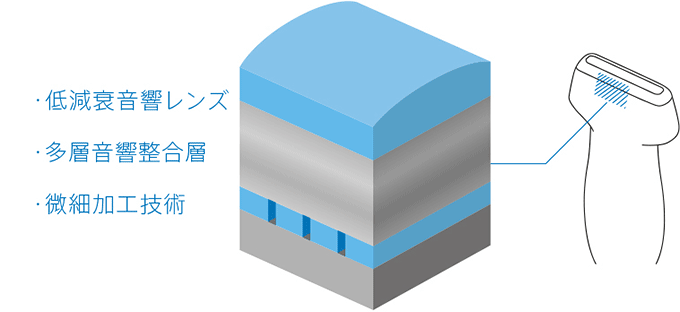

コニカミノルタの挑戦は、「音響センサーの内部で超音波が通過する層の材料をすべて見直す」ことから始まりました。

そして、フィルムメーカーとして培った材料コア技術と高度な加工技術を、音響センサーの開発に応用することで、クラス最高レベルの分解能を持つプローブを実現したのです。

この超広帯域プローブの開発によって、直径数百μm程度の筋束や神経束の繊維構造まで鮮明に描出する高画質な画像を提供することが可能になりました。